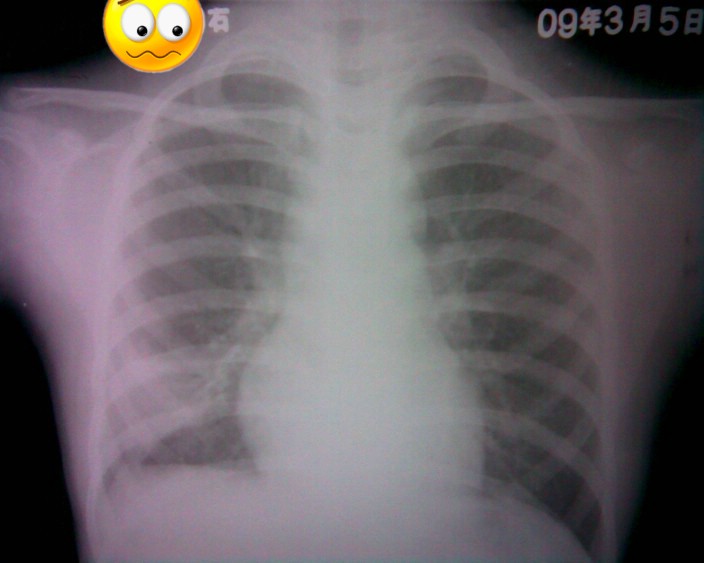

标题: PED1836:女,9岁,发热5天,听诊两肺呼吸音粗 [打印本页]

标题: PED1836:女,9岁,发热5天,听诊两肺呼吸音粗

节段性肺炎。典型!

节段性肺炎。典型!!!

节段性肺炎。片资料完整。